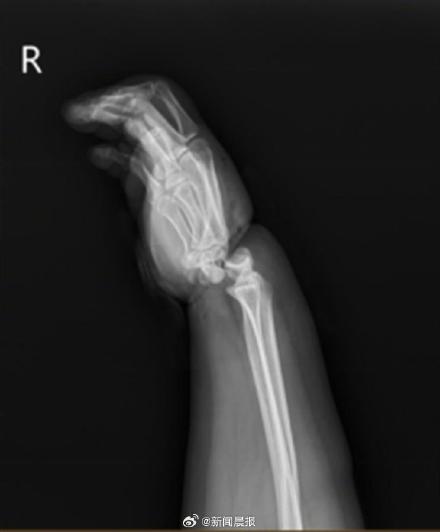

“我刚看到这位患者时,她的右手十分肿胀,手腕严重变形,被绳勒过的皮肤已坏死,整个手掌因缺血呈现青紫色。”宁波二院手显微修复外科副主任郭宗慧向澎湃新闻介绍,经检查发现,小美的腕关节受暴力绞压,两条动脉血管已断,并伴有长段血管损伤,静脉血管出现长段栓塞,手腕关节已完全骨折脱位,有近1cm宽的环形皮肤被挤压坏死。

郭宗慧告诉记者,要想保住小美的手掌,必须尽快恢复手掌的血液流通。然而,小美到医院时距受伤已过去3小时,手掌的毛细血管中已形成血栓,耽误时间越久,手掌因缺血而坏死的可能性越大,医院立即为患者开通绿色通道,紧急开展手术。 手术中,医生先用500毫升抗凝药液为小美疏通手掌血管,再复位腕部断裂和脱位的骨头,然后接通8根血管,修复挫伤的神经,缝合断裂的腕部肌腱,耗时4个多小时为小美“保住”了右手,重建右手血运及功能。